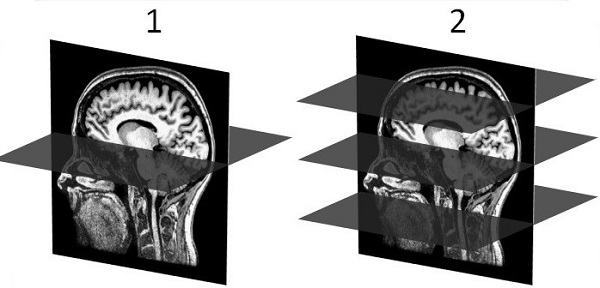

Figure 1. 1 = Normal versus 2 = HyperBand acquisitions